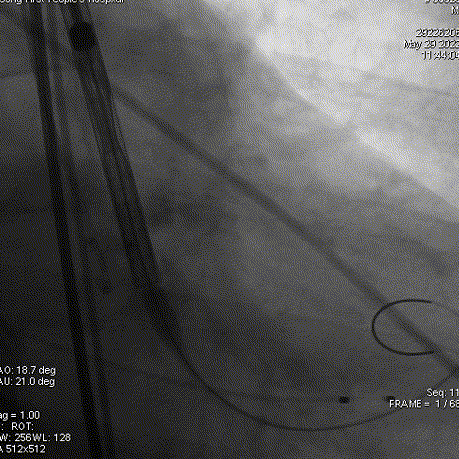

主动脉根部造影

导丝跨瓣

球囊预扩

输送器过弓

瓣膜定位

工作位造影